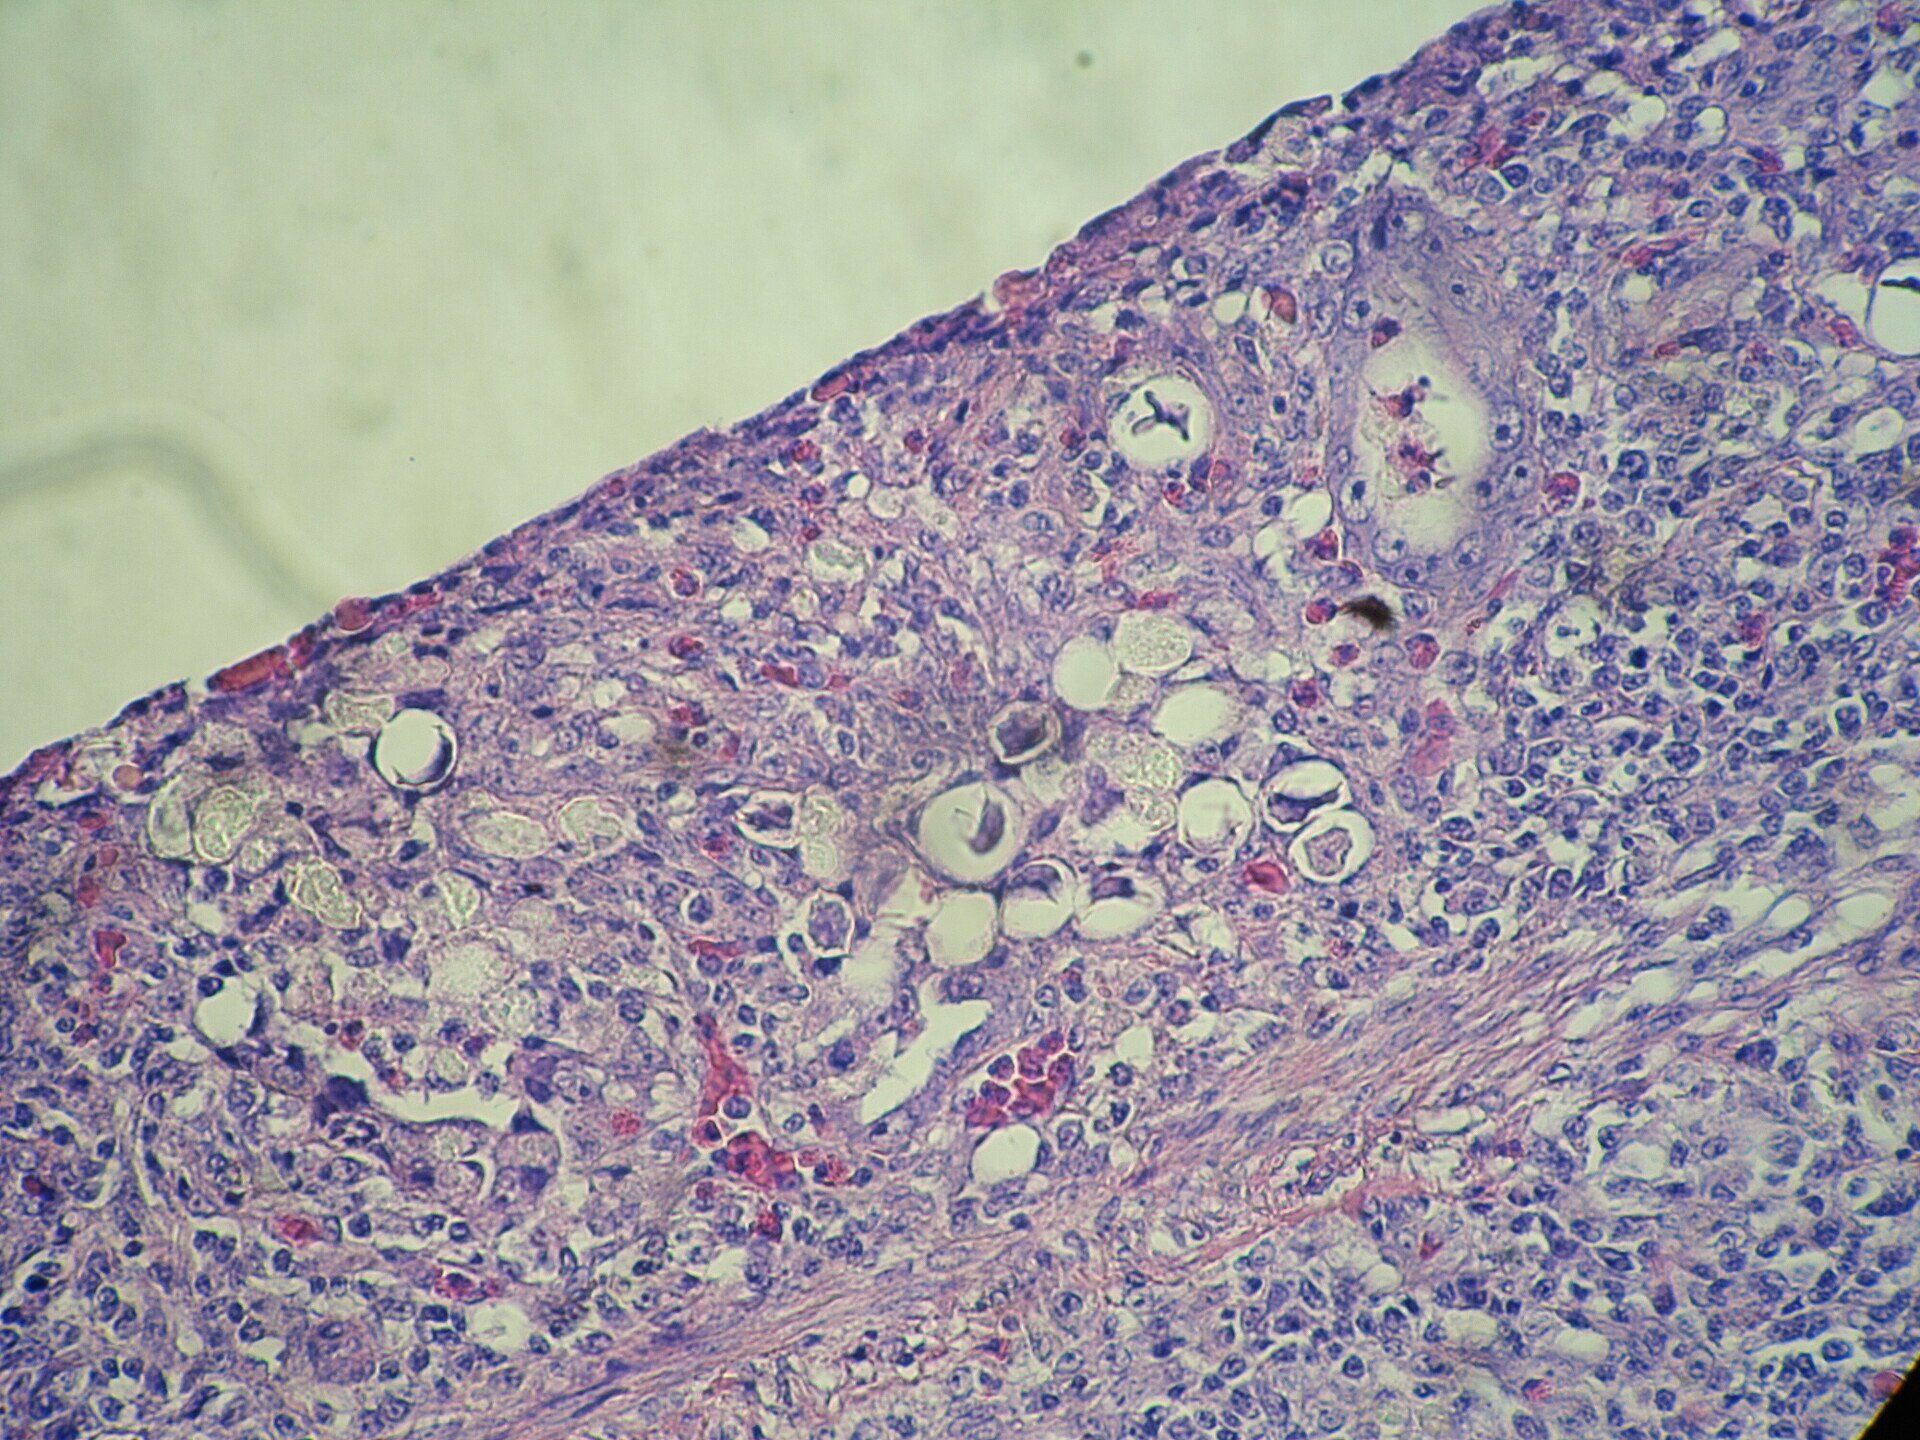

Maladie de Marek

La maladie de Marek est une maladie virale extrêmement contagieuse chez les poules. Elle provoque de très nombreux symptômes liés au développement de tumeurs, des anomalies nerveuses (boiterie) voire de l'abattement. Le diagnostic peut être assez complexe tant cette maladie se présente sous des formes diverses et variées. Elle est malheureusement fatale. La vaccination est généralement pratiquée sur les poussins à l'âge de 1 jour mais n'est pas réalisée en pratique chez les poules de compagnie adulte.